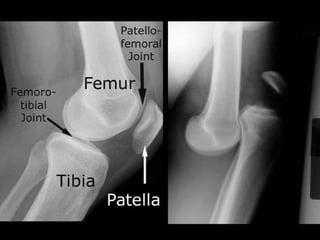

腳掌骨 ( 蹠骨 ) 之壓力性骨折 http://www.mikety.net/X-rays/Fx-mt.ANS.jpeg